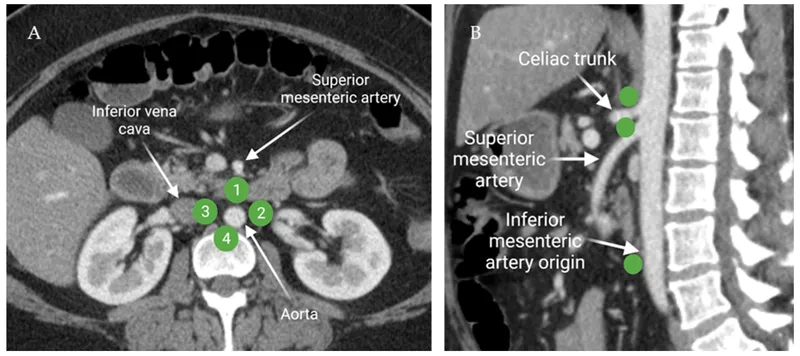

- Pre-aortic Nodes: Drain the GI tract, spleen, pancreas, gallbladder, and liver. They are clustered around the main gut arteries:

- Celiac nodes: Foregut structures.

- Superior Mesenteric (SMA) nodes: Midgut structures.

- Inferior Mesenteric (IMA) nodes: Hindgut structures.

- Para-aortic (Lateral Aortic) Nodes: Drain non-gut organs like kidneys, adrenals, gonads, and the posterior abdominal wall.

- Three main groups of pre-aortic nodes receive lymph from gut derivatives:

- Celiac Nodes: Drain foregut structures (stomach, spleen, liver, pancreas, proximal duodenum).

- Superior Mesenteric Nodes (SMN): Drain midgut structures (distal duodenum to splenic flexure).

- Inferior Mesenteric Nodes (IMN): Drain hindgut structures (descending colon to upper rectum).